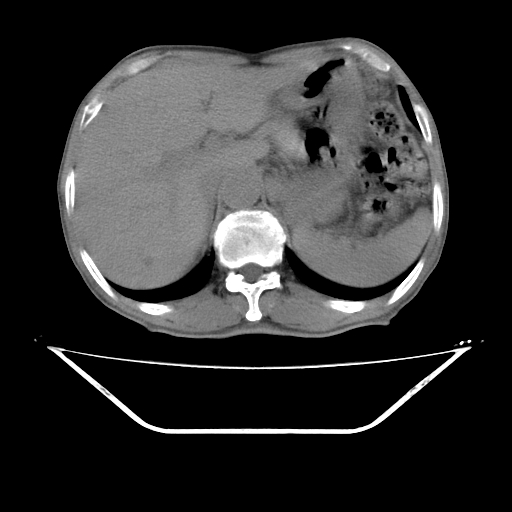

平扫

考虑右肾盂癌,肾动脉受侵,右肾功能减退,右肾盂输尿管积水,管壁增厚,考虑种植转移,应该把下面扫完的

支持右侧肾盂癌伴肾静脉瘤栓形成可能性大,右肾结石.肝右叶后段低密度影,不除外转移.

右肾盂旁ca并肾静脉瘤栓形成/肾功能降低。

右肾结石。

支持 右侧肾盂癌伴肾静脉瘤栓形成可能性大,右肾结石;肝右叶后段低密度影,不除外转移。

1.右侧肾盂癌伴肾盂积水。

2.肾脏功能减退,原因有:(1)肾动脉受侵。(2)肾静脉受侵(3)肾积水,等。本例,肾动脉显影较好,但受压明显;肾静脉无明显显示,受压或静脉癌栓,下腔静脉腔内未见明显充盈缺损。

3.右侧上段输尿管扩张,原因:(1)积水所致;(2)种植。